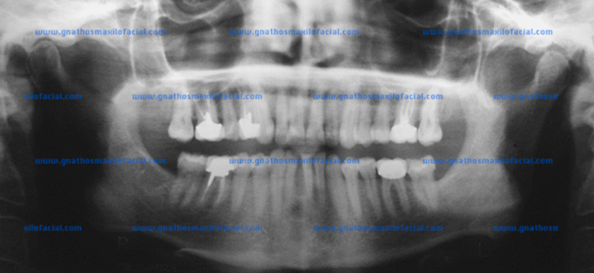

Los terceros molares al quedarse retenidos dentro del hueso pueden causar muchos problemas. Se pueden formar quistes de grandes dimensiones a partir del tejido que forma el tercer molar, destruyendo parte del hueso y dañando los dientes vecinos o reabsorbiendo sus raices

|

| Quiste dentígero relacionado a la corona de un tercer molar inferior izquierdo retenido. Arriba también hay otro quiste relacionado al canino (flechas) |

Si un quiste dentigero se deja sin tratamiento, se desarrollará la lesión hasta producir destrucción ósea importante. Consecuentemente, el manejo será muy radical en comparación con la simple extracción y enucleación de la lesión en etapas tempranas.